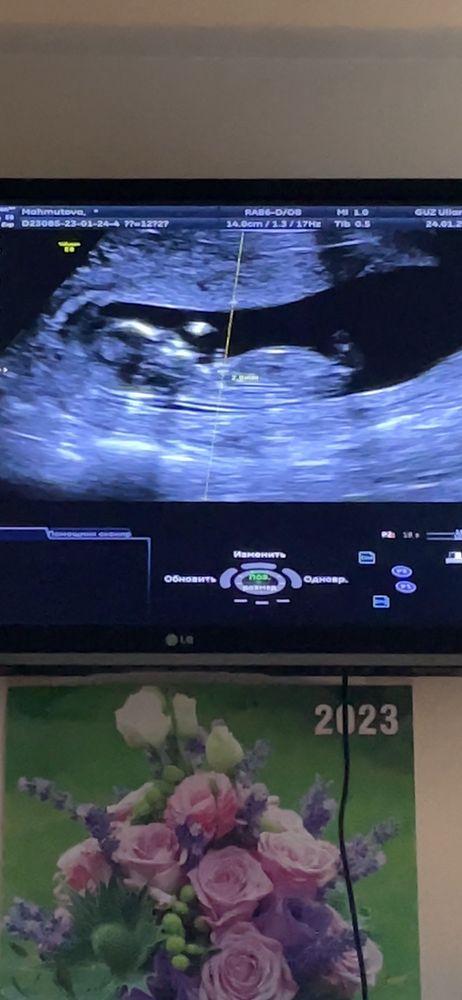

На первом фото половой бугорок паралельно расположен,не под углом, девочка, наверное.

Алина, там недель 13 на фото? На этом сроке пол в этом ракурсе не смотрят, т.к. половых органов еще нет как таковых, а половой бугорок торчит у всех, и у мальчиков, и у девочек. Но это все равно все не точно пока, точно пол может увидеть с 15-16 недель.

Чашка утреннего кофе, да, 13 недель , врач на 3 фото сказал торчит как у пацана) но я не верю)